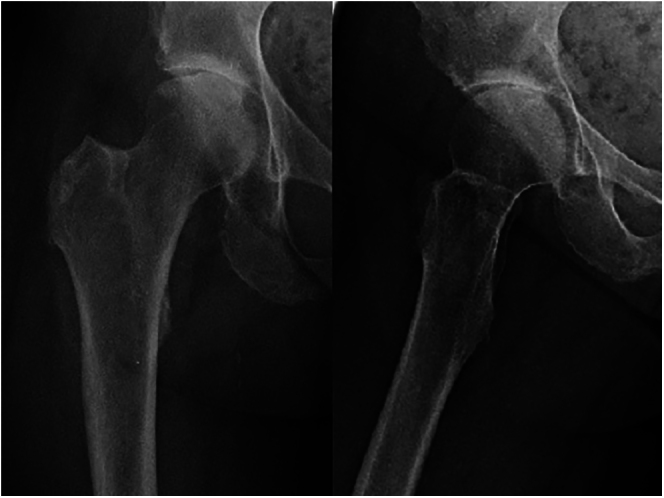

酪氨酸钾尿症是一种极其罕见的酪氨酸代谢疾病,由常染色体隐性遗传的同源戊二酸(HGA)氧化酶缺乏症引起,会导致酪氨酸在胶原结构中蓄积,尤其是在透明软骨中。该病的特征是同型戊二酸尿症、结缔组织蓝黑色褪色(chronosis)以及脊柱和大型负重关节的关节病。该病有多种临床表现,包括冠状动脉和瓣膜钙化、主动脉狭窄、胸部扩张受限、肾结石、尿道结石和前列腺结石以及眼部和皮肤色素沉着。骨骼病变通常表现为脊柱的脊椎病变。膝关节是最常见的受累外周关节。可能会出现腱鞘炎或肌腱断裂,骨密度降低也并不罕见。低蛋白饮食和抗坏血酸可降低 HGA 水平。尼替西酮可以安全有效地减少 HGA 的产生和尿液排泄。对于严重的chronotic关节病,关节置换术可提供可靠的疼痛缓解和良好的功能效果。对年轻患者来说,无水泥固定是一种成功的方法。

Alkaptonuria is an extremely rare disorder of tyrosine metabolism caused by an autosomal recessive enzymatic deficiency of homogentisic acid (HGA) oxidase, causing its accumulation in collagenous structures, especially in hyaline cartilage. It is characterized by a triad of homogentisic aciduria, bluish-black discoloration of connective tissues (ochronosis) and arthropathy of the spine and large weight-bearing joints. Several clinical manifestations were described including coronary and valvular calcification, aortic stenosis, limited chest expansion, and renal, urethral and prostate calculi as well as ocular and cutaneous pigmentation. Skeletal affection usually presents as spondylotic changes of the spine. The knee is the most common peripheral joint to be involved. Enthesopathy or tendon ruptures may occur, and reduced bone density is not unusual. A low-protein diet and ascorbic acid may reduce HGA levels. Nitisinone can safely and effectively reduce HGA production and urinary excretion. In severe ochronotic arthropathy, joint arthroplasty can offer reliable pain relief and excellent functional outcomes. Cementless fixation is successful in young patients.